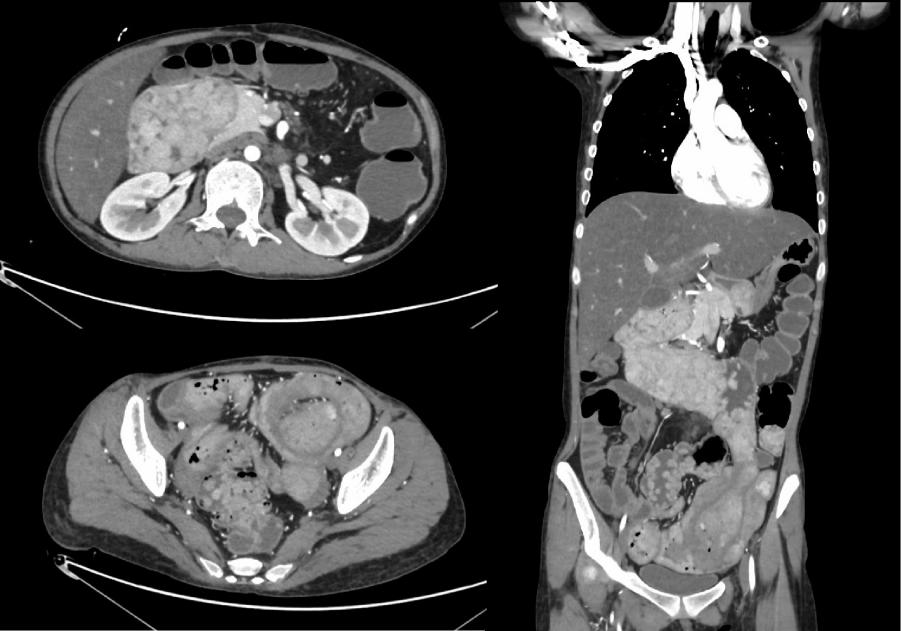

声检查  小器官超声提示甲状腺双叶多发囊性结节(C-TIRADS 2类)。乳腺及腋窝淋巴结未见明显异常。小肠CT三维重建(图1)提示:① 胃窦区、小肠、结肠多发结节肿块,符合P-J综合征影像学表现;② 左下腹肠套叠;③ 中度脂肪肝;④ 肠系膜根部多发肿大淋巴结;⑤ 肝左叶低密度结节,建议随访;⑥ 宫颈多发囊肿。

图1:十二指肠、空肠、回肠多发结节状密度增高影,左下腹肠套叠。

2025年7月复查,妇科术后稳定。2025年12月患者于消化科复查,入院时乏力,间断出现双手、下肢痉挛及手足麻木感,食欲一般,体重较前下降,BMI:15.46 kg/m2,,呈贫血貌,颜面部及下肢水肿。实验室检查提示,血红蛋白 96.00 g/L,血小板计数 628.00×109/L,钾 2.51 mmol/L,钙 1.22 mmol/L,白蛋白 15.56 g/L,便潜血试验阳性。复查小肠CTE提示:① 消化道多发结节肿块,符合P-J综合征影像学表现;② 重度脂肪肝;③ 全子宫+双侧附件切除术后改变;盆腔及双侧腹股沟区多发较大淋巴结,同前相仿;④ 腹腔、盆腔积液,较前稍增多。